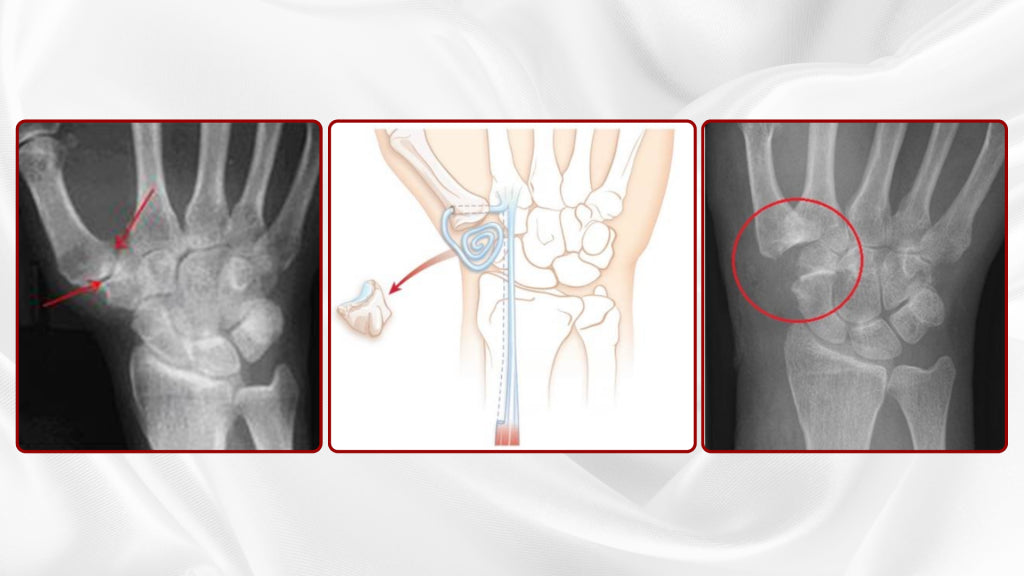

Arthritis Surgery

Years of motion leads to changes in the cartilage of all the joints, the so-call degenerative arthritis or Osteoarthitis. Osteoarthritis affects everyone. Surgical therapy becomes necessary when conservative treatments show no success (anymore).